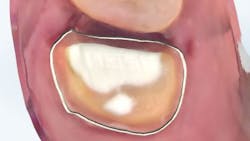

In the case below, tooth No. 2 was diagnosed with symptomatic irreversible pulpitis and symptomatic apical periodontitis with a mesial marginal ridge fracture due to extensive caries (figure 1). Root canal therapy and a full coverage crown were recommended and the patient accepted.

The carious tissue was removed, followed by the endodontic procedure and subsequent placement of the build-up. Despite the deep extent of mesial decay, a clear and accurate scan was achieved (figure 2).

The iTero scanner was able to clearly define the delineation between the soft and hard tissue as can be seen in this image of the digital die trim (figure 3). Radiographs were captured on delivery revealing a clinically acceptable outcome for the patient (figure 4). Direct restorations were completed on teeth Nos. 3 and 4 during this visit.